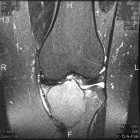

23 year old female with pain in left knee for three months

Zoom image: Cell stain Cell stain.

Zoom image: Radiological image Radiological image.